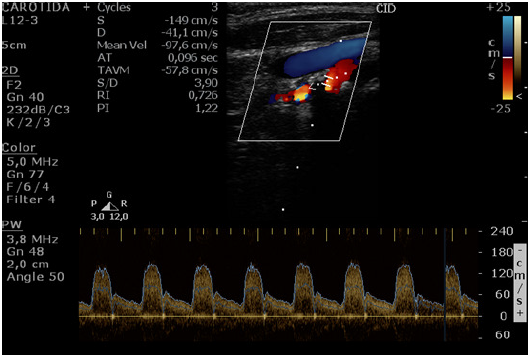

A imagem abaixo refere-se a Doppler de carótida interna

Considerando o Consenso da Sociedade de Radiologia (Society of Radiologist in Ultrasound Consensus Conference - Grant et al., 2003) o diagnóstico mais provável é de

Estenose carotídea de 20% a 49%

Estenose carotídea de 51% a 60%

Estenose carotídea ≥ 70%

Estenose carotídea de 50% a 69%

Estenose carotídea de 60% a 79%